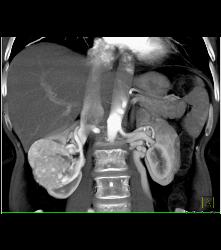

Scarring in Right Kidney